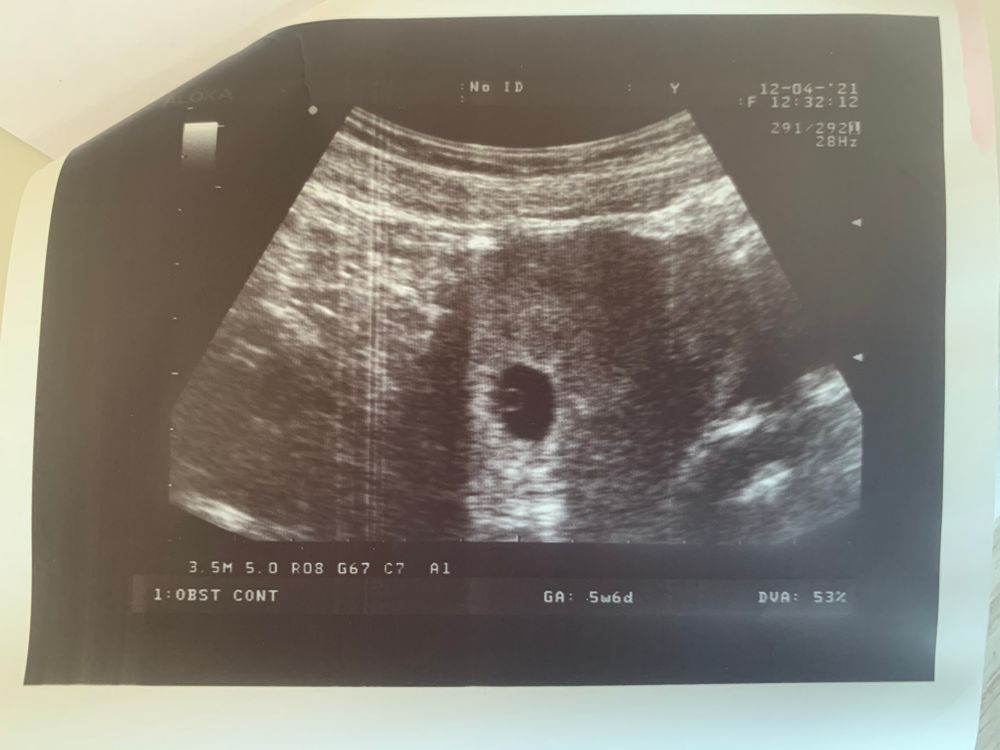

Узи на 6 неделе

Сделали узи, все хорошо, нету никаких угроз🙏🏻. По узи поставили 5 недель, пя 16 мм, СБ пока не визиолизируеться. Сказали прийти через неделю.